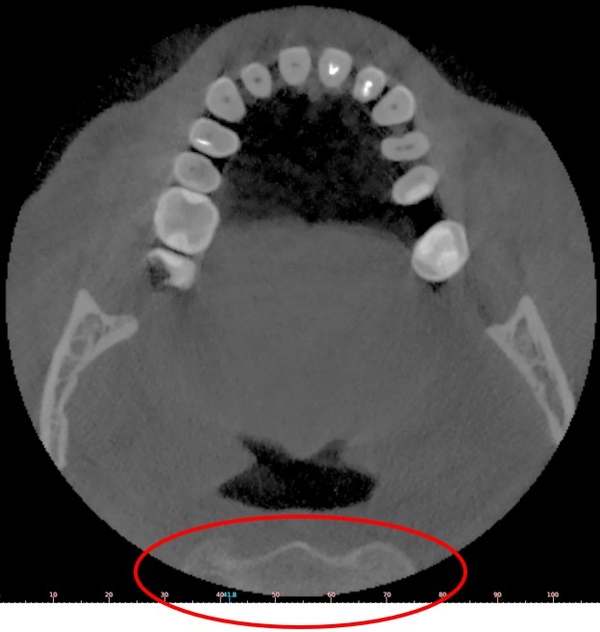

Ampliando il diametro dell’indagine si rischia però di incorrere nel problema opposto, ovvero sconfinare dall’area dentale e sottoporre a irraggiamento aree e organi non di interesse odontoiatrico e peraltro molto sensibili ai raggi X quali, ad esempio, il rachide.

Nella figura, una sezione assiale di una CBCT con diametro 110mm nella quale compare il rachide

Includere aree non riguardanti l’ambito odontoiatrico introduce diverse problematiche: innanzitutto stiamo irraggiando delle zone al di fuori della nostra competenza, quindi la maggior dose somministrata al paziente non avrebbe una giustificazione, come indicato dai principi di radioprotezione del D. Lgs. 230/95. Secondariamente avremmo delle responsabilità sia legali che etiche e deontologiche sull’analisi delle immagini ottenute e che rappresentano aree al di fuori della nostra competenza clinica. Infine, le zone irraggiate rappresentano comunque un ostacolo all’acquisizione delle arcate dentali, comportando un deterioramento della qualità delle immagini delle arcate dentali rispetto alla possibilità di poterle acquisire senza che le radiazioni debbano attraversare il rachide.